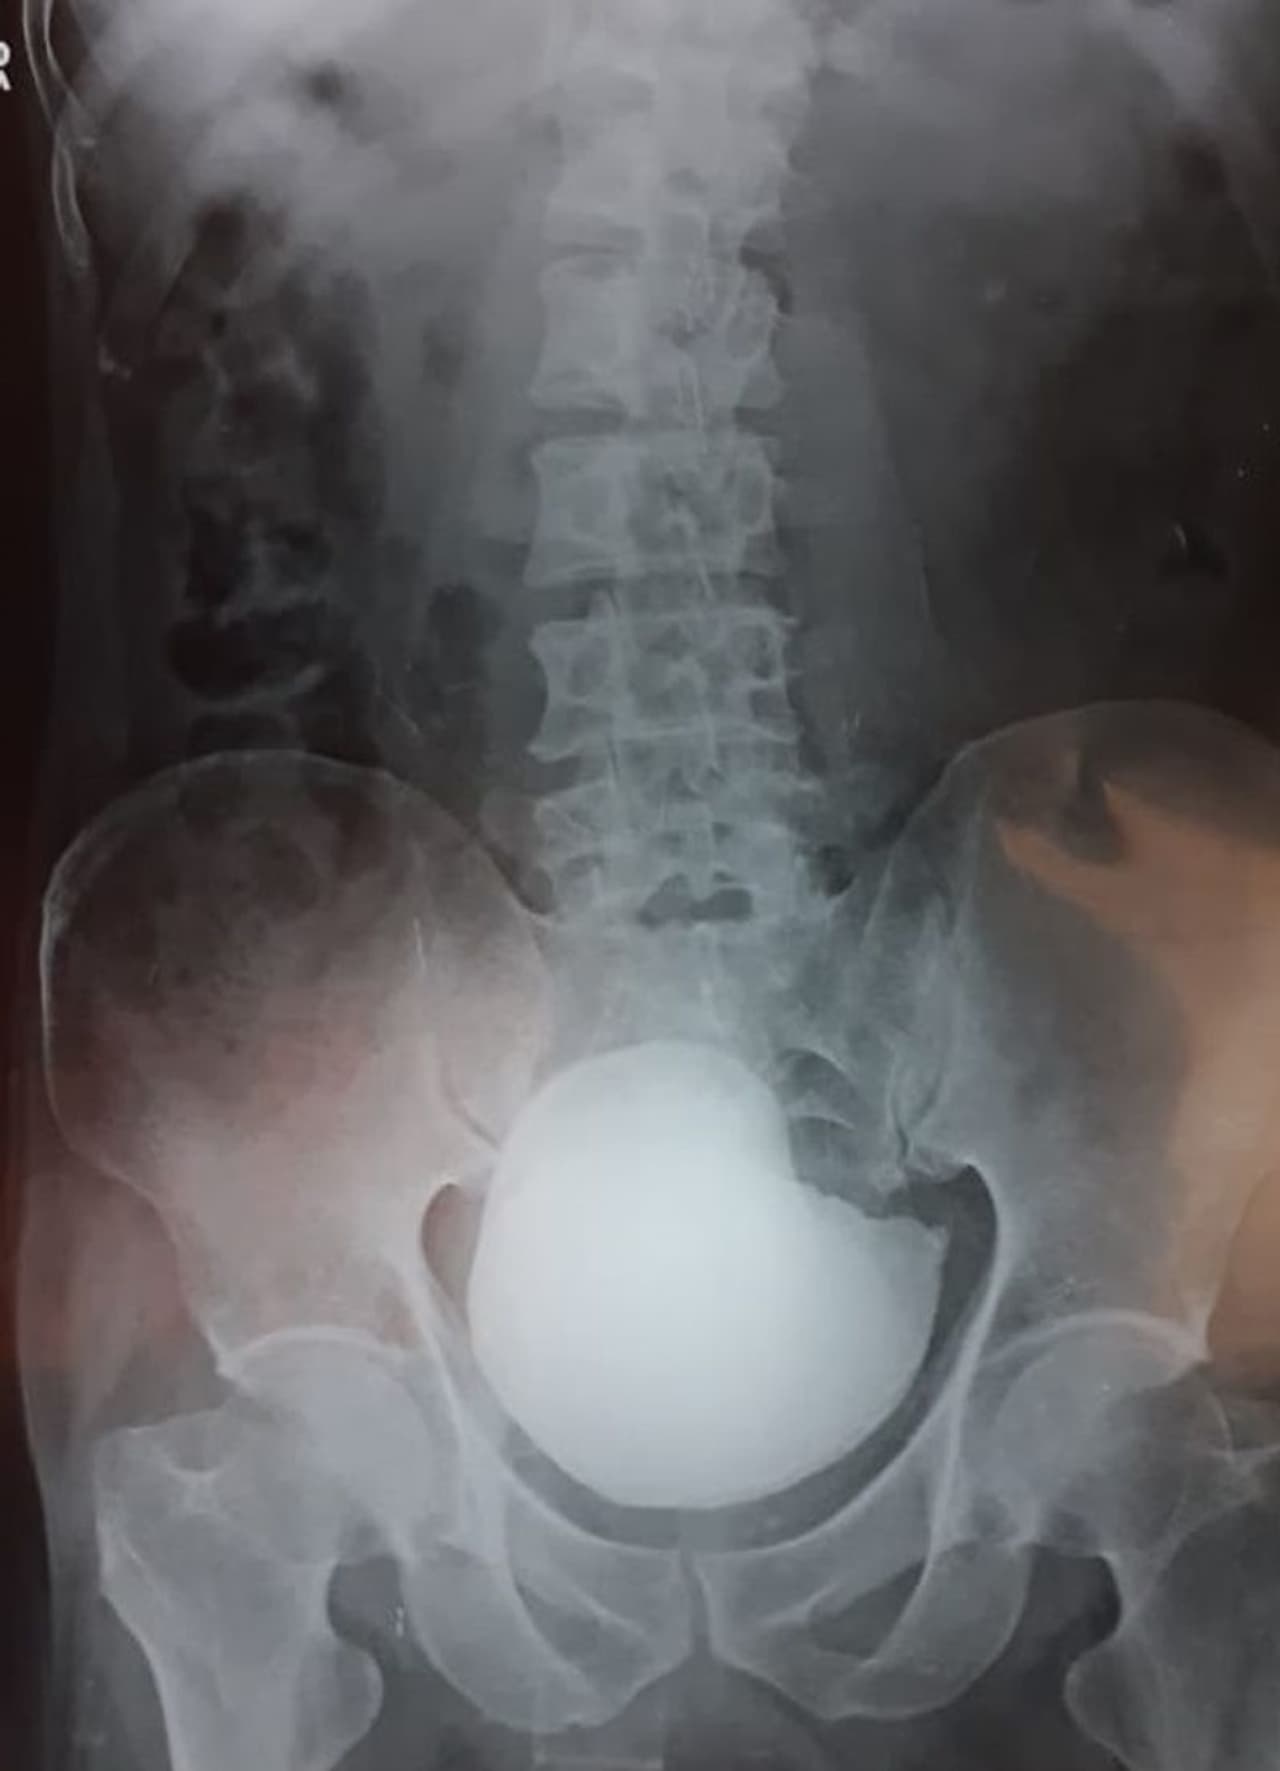

ವ್ಯಕ್ತಿಯ ಮೂತ್ರಕೋಶದಲ್ಲಿ ಕಲ್ಲು ಪತ್ತೆ ಹಚ್ಚಿದ ವೈದ್ಯರು| ಶಸ್ತ್ರಚಿಕಿತ್ಸೆಯ ಮೂಲಕ ಕಲ್ಲು ತೆಗೆದ ವಿಜಯಪುರ ನಗರದ ಭಾಗ್ಯವಂತಿ ಆಸ್ಪತ್ರೆಯ ವೈದ್ಯರು| ಶಸ್ತ್ರಚಿಕಿತ್ಸೆ ಮಾಡುವ ಮೂಲಕ 750 ಗ್ರಾಂ ತೂಕದ ಕಲ್ಲು ಹೊರತೆಗೆಯುವಲ್ಲಿ ಯಶಸ್ವಿಯಾದ ವೈದ್ಯರ ತಂಡ|

ವಿಜಯಪುರ(ಜೂ.10): ವೈದ್ಯಕೀಯ ಲೋಕದಲ್ಲಿ ಅಪರೂಪದ ಶಸ್ತ್ರಚಿಕಿತ್ಸೆಯನ್ನ ನಗರದ ವೈದ್ಯರು ಮಾಡಿದ್ದಾರೆ. ಹೌದು, ಮೂತ್ರಕೊಶದ ಸಮಸ್ಯೆಯಿಂದ 48 ವರ್ಷದ ವ್ಯಕ್ತಿಯೊಬ್ಬರು ಭಾಗ್ಯವಂತಿ ಆಸ್ಪತ್ರೆಯಲ್ಲಿ ದಾಖಲಾಗಿದ್ದರು. ವೈದ್ಯರು ಎಕ್ಸರೇ ತೆಗೆದು ನೋಡಿದಾಗ ವ್ಯಕ್ತಿಯ ಮೂತ್ರಕೋಶದಲ್ಲಿ ಬೃಹತ್ ಗಾತ್ರದ ಕಲ್ಲೊಂದು ಪತ್ತೆಯಾಗಿತ್ತು.

ವೈದ್ಯಕೀಯ ಭಾಷೆಯಲ್ಲಿ ಗೇಂಟ್ ವೆಸೈಕಲ್ ಕ್ಯಾಲಕ್ಯೂಲಸ್ ಅಥವಾ ಲಾರ್ಜ್ ಯುರಿನರಿ ಬ್ಲ್ಯಾಡರ್ ಸ್ಟೋನ್ ಎಂದು ಈ ರೋಗವನ್ನ ಕರೆಯಲಾಗುತ್ತದೆ. ಮೂತ್ರ ಸರಿಯಾಗಿ ಹೋಗದೇ ಇರುವುದು, ಮೂತ್ರ ತಡೆಯಿಯುವುದರಿಂದ ಈ ಸಮಸ್ಯೆ ಉಂಟಾಗುತ್ತದೆ.

ಹೀಗಾಗಿ ಭಾಗ್ಯವಂತಿ ಆಸ್ಪತ್ರೆಯ ಡಾ. ಅಶೋಕ ಬಿರಾದಾರ ಹಾಗೂ ತಂಡ ಶಸ್ತ್ರಚಿಕಿತ್ಸೆ ಮಾಡುವ ಮೂಲಕ 750 ಗ್ರಾಂ ತೂಕದ ಕಲ್ಲು ಹೊರತೆಗೆಯುವಲ್ಲಿ ಯಶಸ್ವಿಯಾಗಿದ್ದಾರೆ. ವೈದ್ಯಕೀಯ ಲೋಕದಲ್ಲಿ ಇಷ್ಟು ದೊಡ್ಡ ಕಲ್ಲು ಪತ್ತೆಯಾಗಿದ್ದು ಅಪರೂಪ ಪ್ರಕರಣ ಇದಾಗಿದೆ ಎಂದು ಹೇಳಲಾಗುತ್ತಿದೆ.